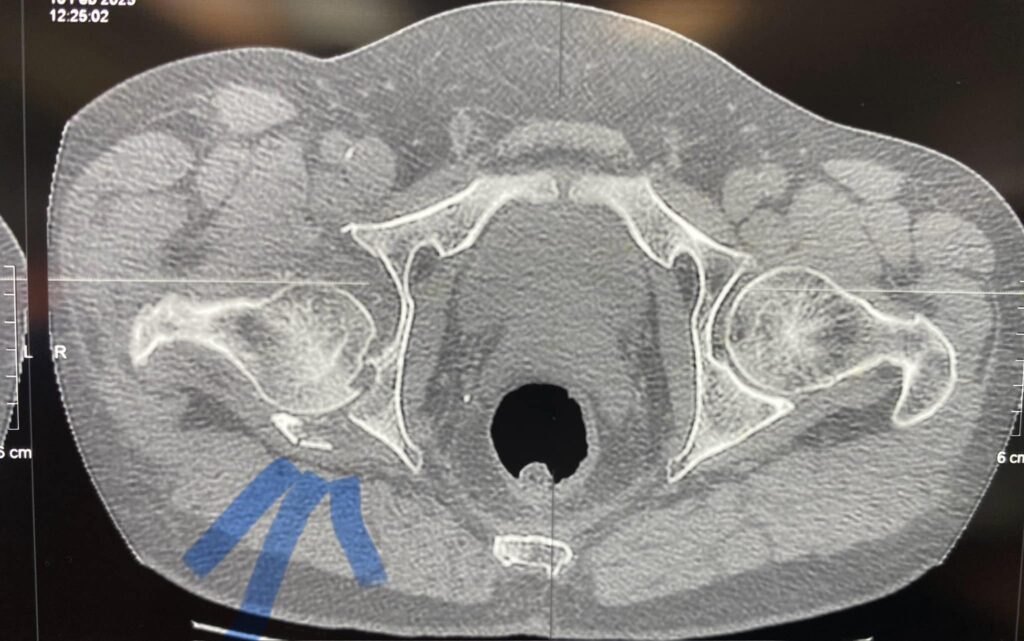

Тут вы видите рентгенограммы двух пациентов. В одном случае ранение голени у коленного сустава. В другом случае у сустава голеностопного с переломом костей. Поэтому там пластина еще стоит.

Обоим раненым (а каждый из них лечится по полгода уже) проведены по несколько операций дебридмента («чистка» кости и мягких тканей). К сожалению, это не остановило инфекцию.

В общем, все чаще и чаще приходится травматологам в Украине применять Bonalive. Это заменитель кости с антибактериальным действием. Только вот действует этот заменитель (финского производства) не за счет антибиотиков. Их в нем нет. А за счет того, что резко меняет Ph среды в кислую сторону. Бактерии погибают, привыкания к этому заменителю нет и быть не может (пока и если не появится какой-то новый, доселе неизвестный микроб), рост же собственной кости резко стимулируется.

Bonalive, как и всякий современный препарат высокотехнологичного производства, очень и очень дорог. Вот такой шприц-контейнер, как на фото, с 10 «кубиками» препарата стоит 500 евро (плюс-минус несколько процентов в зависимости от величины поставки).

Эти двое пациентов, чьи рентгенограммы вы видите, были прооперированы Председателем нашей Ассоциации AO Trauma Ukraine Олександром Рихтером в одном из военных госпиталей на западе Украины. Все зажило отлично.

Для первого раненого хватило 10 кубических сантиметров Bonalive, на второго – там, где пластина, ушло 20 «кубиков». Итого, в дополнение ко всему прочему – это 1500 евро.